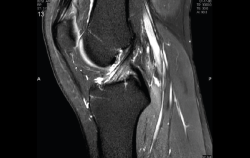

1.2.2. Ligamento cruzado anterior (LCA) (Figuras 40, 41, 42, 43 y 44)

Figura 40. Corte de secuencia sagital T2 Fat-Sat de resonancia magnética de rodilla: ligamento cruzado anterior normal.

Figura 41. Cortes de secuencia sagital T2 Fat-Sat de resonancia magnética de rodilla: rotura central del ligamento cruzado anterior.

Figura 42. Cortes de secuencia sagital T2 Fat-Sat: rotura proximal del ligamento cruzado anterior.